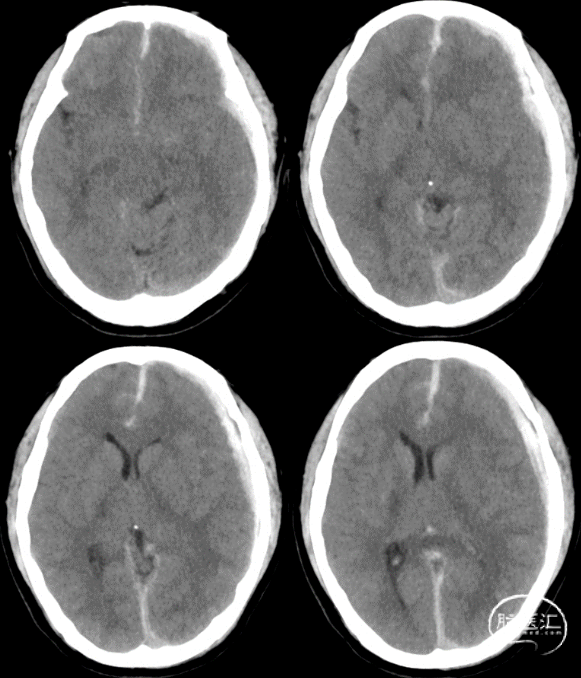

4.头颅CT(2022-10-22):

1.创伤性蛛网膜下腔出血

2.左侧额颞顶部硬膜下血肿

3.大脑镰下疝

4.右侧颞极蛛网膜囊肿